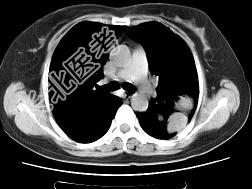

- 患者胸痛胸闷,CT如图, 最可能的诊断为